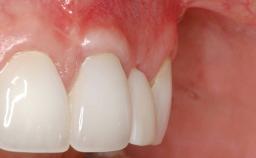

A 30-year-old woman was referred by her general dentist for evaluation of an esthetic complication related to previous implant treatment for congenitally missing maxillary lateral incisors. The patient’s chief complaint was the inadequate esthetic appearance of her smile. The case demonstrates the use of a combined approach to achieve optimal results. Two different flap designs - a tunnel technique and a coronally advanced flap - are employed based on the surgical objectives for the affected site.